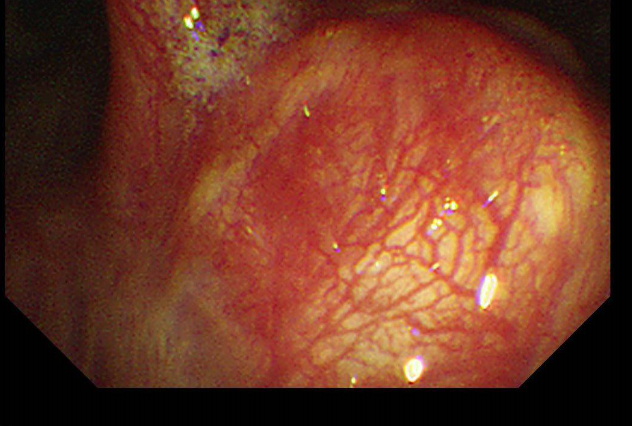

该患者因反复咳嗽、气促就诊,经CT及支气管镜检查,发现右肺主气管内有一约1.7cm的肿物,病理确诊为支气管低度恶性肿瘤。传统手术需切除整个右肺,但考虑到患者肺功能及生活质量,我院胸心大血管外科主任马海涛教授团队决定采用创伤更小的“支气管袖式切除术”——在完整切除肿瘤的同时,将健康支气管断端吻合,最大限度保留健康肺组织。手术历时3小时余,术中快速病理确认切缘无肿瘤残留。术后患者未出现并发症,肺功能恢复理想。